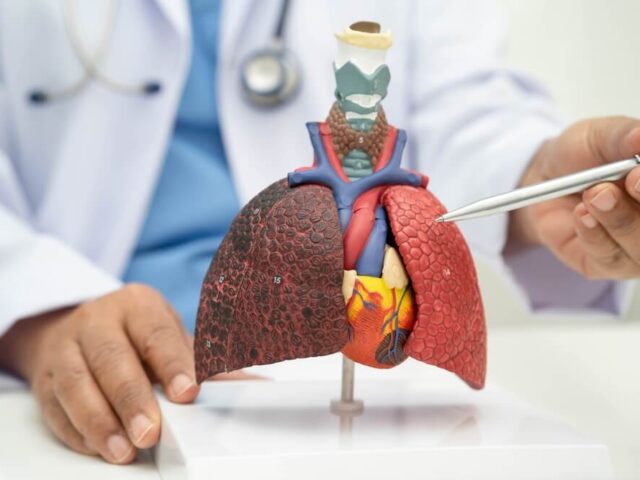

Pročitajte višeHronična opstruktivna bolest pluća: Simptomi, uzroci i lečenje

Disanje je nešto o čemu većina ljudi ne razmišlja dok god funkcioniše normalno. Međutim, kada penjanje uz stepenice, kraća šetnja,...